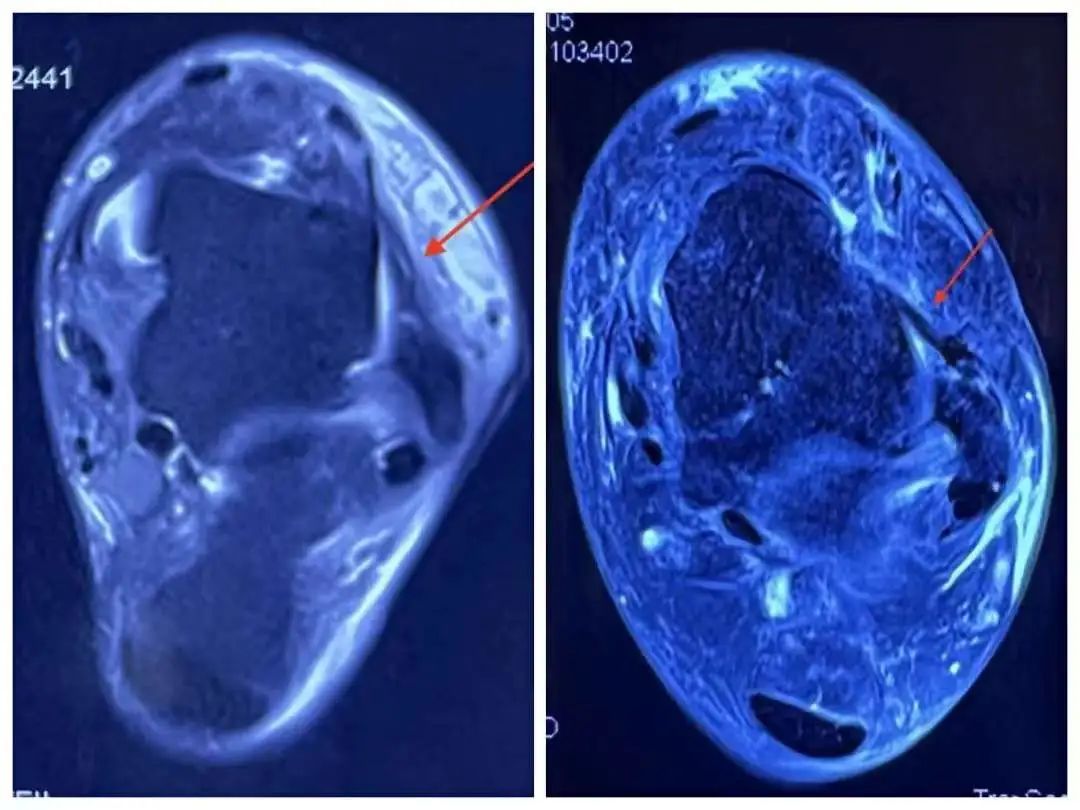

术前术后磁共振对比

踝关节距腓前韧带损伤属于关节囊内韧带结构,传统切开手术方式属于由外向内,术中需切开关节囊暴露韧带,不可避免造成关节囊的损伤,术后出现出血、粘连等并发症;科室采用全关节镜下韧带修补术,在关节镜监视下于关节囊内缝合韧带,避免了切开手术的弊端,同时术中还可以一并处理关节内的其他病变,取得了良好的疗效。